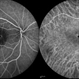

- Atypical central serous chorioretinopathy

- chronic central serous chorioretinopathy (CSCR), retinal pigment epithelium atrophy

- Left eye extensive RPE atrophy at macula from chronic central serous chrioretinopathy in a 62-year-old gentleman. The right eye had a similar picture.